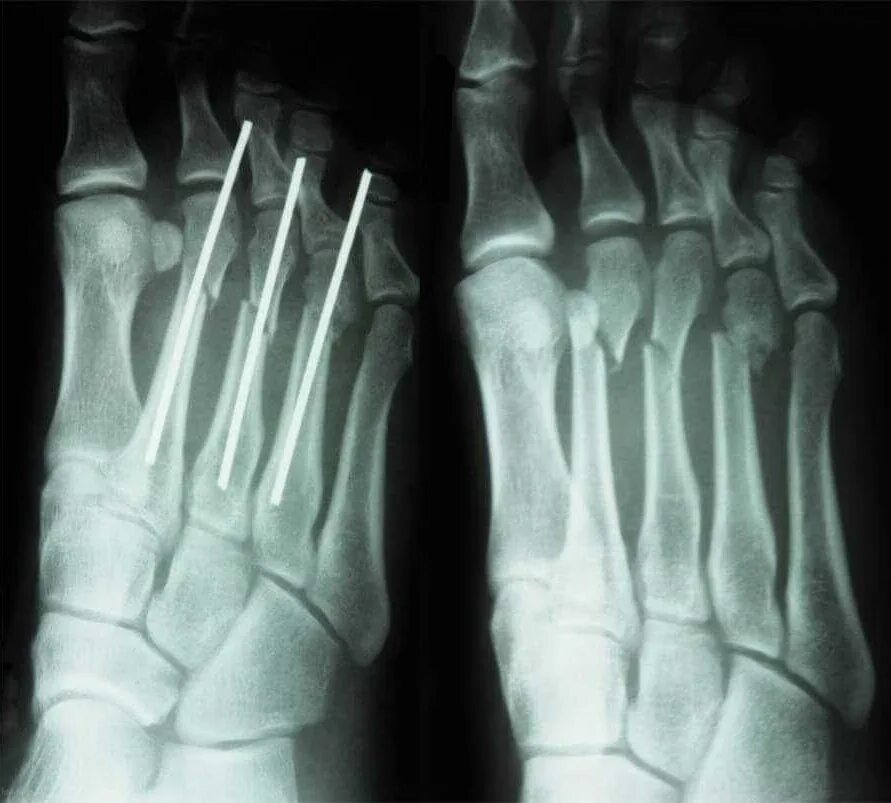

Лечить перелом стопы